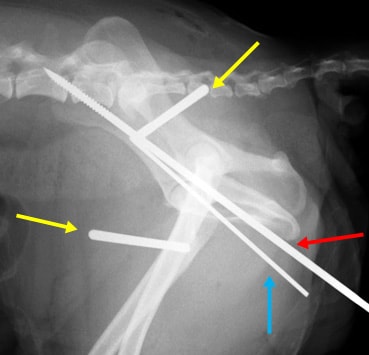

股関節脱臼① 関節包再建術とDeVitaピン法と伸縮性創外固定装置を併用して整復した一例

関節包再建術後、大腿骨頭の背側脱臼を防ぐためのDeVitaピンを挿入します。(赤矢印)

DeVitaピン(赤矢印)とクロスピン(青矢印)を挿入後、大腿骨の外旋を防ぎ、